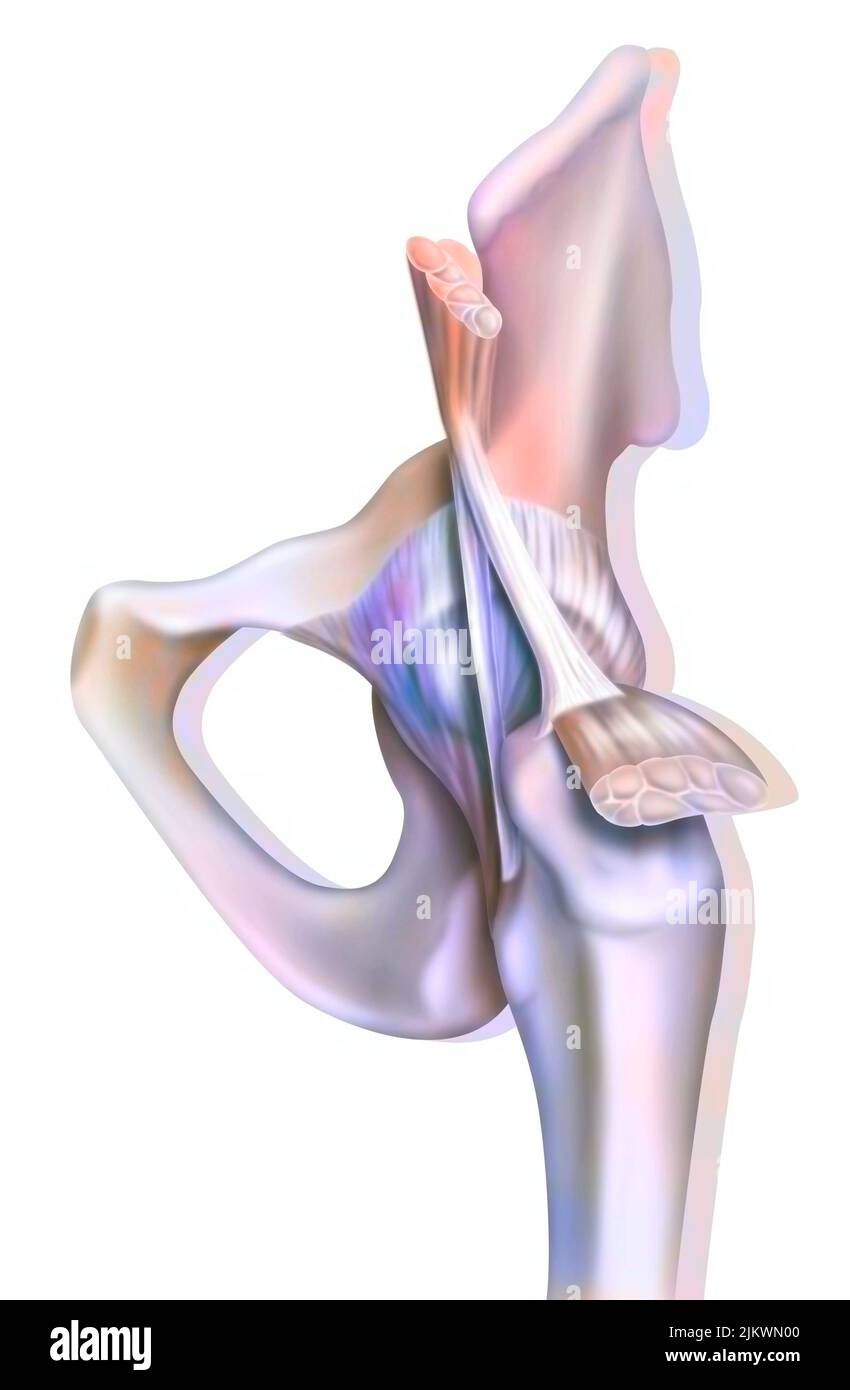

Bone joint of the hip without and with the coxofemoral joint capsule. Stock Photohttps://www.alamy.com/image-license-details/?v=1https://www.alamy.com/bone-joint-of-the-hip-without-and-with-the-coxofemoral-joint-capsule-image476923594.html

Bone joint of the hip without and with the coxofemoral joint capsule. Stock Photohttps://www.alamy.com/image-license-details/?v=1https://www.alamy.com/bone-joint-of-the-hip-without-and-with-the-coxofemoral-joint-capsule-image476923594.htmlRF2JKWMWE–Bone joint of the hip without and with the coxofemoral joint capsule.

Bone joint of the hip without and with the coxofemoral joint capsule. Stock Photohttps://www.alamy.com/image-license-details/?v=1https://www.alamy.com/bone-joint-of-the-hip-without-and-with-the-coxofemoral-joint-capsule-image476923691.html

Bone joint of the hip without and with the coxofemoral joint capsule. Stock Photohttps://www.alamy.com/image-license-details/?v=1https://www.alamy.com/bone-joint-of-the-hip-without-and-with-the-coxofemoral-joint-capsule-image476923691.htmlRF2JKWN0Y–Bone joint of the hip without and with the coxofemoral joint capsule.

Anatomy of the coxofemoral (hip) joint with muscles, tendons. Stock Photohttps://www.alamy.com/image-license-details/?v=1https://www.alamy.com/anatomy-of-the-coxofemoral-hip-joint-with-muscles-tendons-image476923600.html

Anatomy of the coxofemoral (hip) joint with muscles, tendons. Stock Photohttps://www.alamy.com/image-license-details/?v=1https://www.alamy.com/anatomy-of-the-coxofemoral-hip-joint-with-muscles-tendons-image476923600.htmlRF2JKWMWM–Anatomy of the coxofemoral (hip) joint with muscles, tendons.

Anatomy of the coxofemoral (hip) joint with muscles, tendons. Stock Photohttps://www.alamy.com/image-license-details/?v=1https://www.alamy.com/anatomy-of-the-coxofemoral-hip-joint-with-muscles-tendons-image476923664.html

Anatomy of the coxofemoral (hip) joint with muscles, tendons. Stock Photohttps://www.alamy.com/image-license-details/?v=1https://www.alamy.com/anatomy-of-the-coxofemoral-hip-joint-with-muscles-tendons-image476923664.htmlRF2JKWN00–Anatomy of the coxofemoral (hip) joint with muscles, tendons.